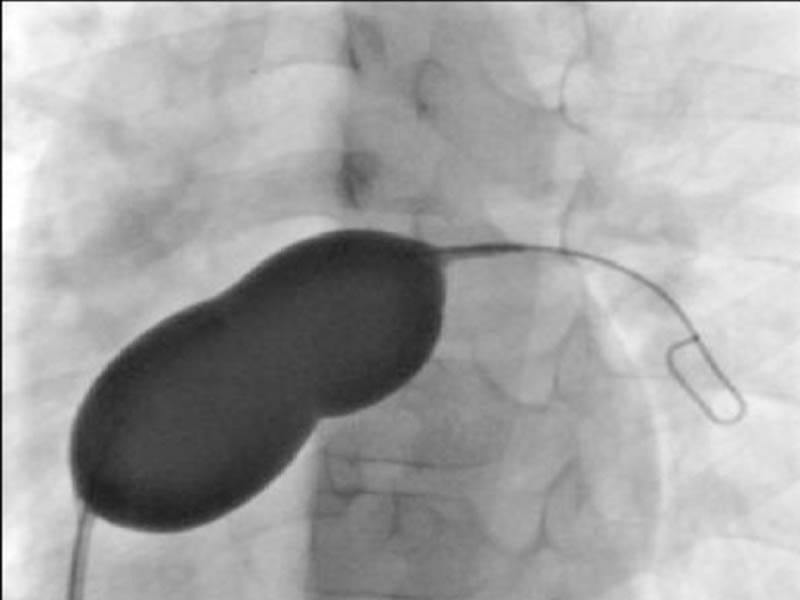

Interventions For Congenital And Structural Heart Disease